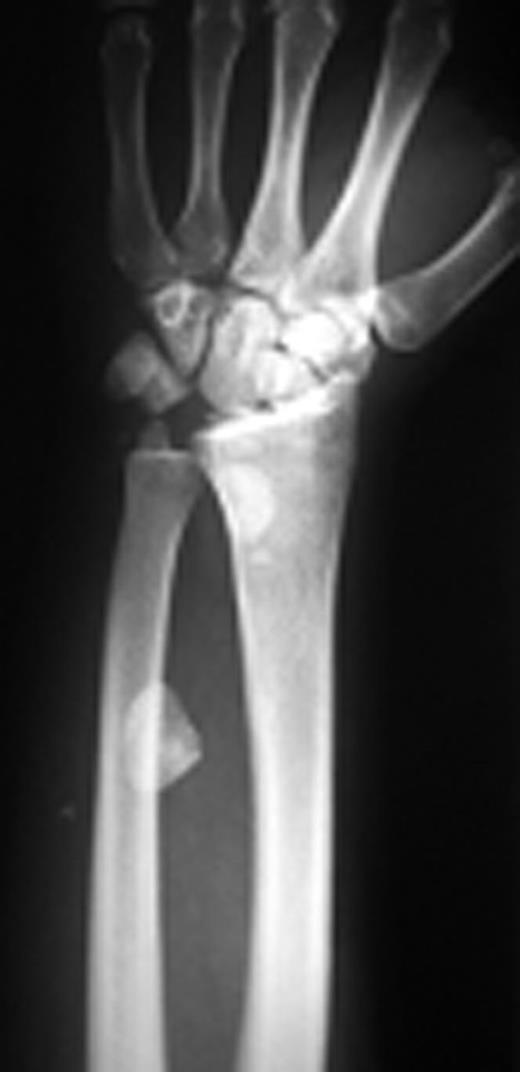

Pins were removed six weeks later, and the cast was discarded ten weeks later. Active and passive range of wrist motion and muscle strengthening exercises were begun. The patient didn’t refer for follow-ups. After two years, he came back with pain, limited motion, and weakness in grip and grasp. Radiographs showed osteonecrosis of lunate and proximal scaphoid. Also, static scapholunate dissociation with signs of mild arthritis was obvious (Figure 2a & 2b).

Posteroanterior and lateral radiographs of left wrist two years after operation show increased density of lunate and proximal scaphoid with subtle arthritic changes. Scapholunate dissociation (Terry-Thomas sign) and dorsal intercalated segment instability are seen.